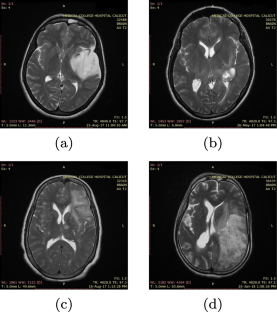

Computer aided diagnosis using artificial intelligent techniques made tremendous improvement in medical applications especially for easy detection of tumor area, tumor type and grades. This paper presents automatic glioma tumor grade identification from magnetic resonant images using Wndchrm tool based classifier (Weighted Neighbour Distance using Compound Heirarchy of Algorithms Representing Morphology) and VGG-19 deep convolutional neural network (DNN). For experimentation, DICOM images are collected from reputed government hospital and the proposed intelligent system categorized the tumor into four grades such as low grade glioma, oligodendroglioma, anaplastic glioma and glioblastoma multiform. After preprocessing, features are extracted, optimized and then classified using Windchrm tool where the most significant features are selected on the basis of Fisher score. In the case of DNN classifier, data augmentation is also performed before applying the images into the deep learning network. The performance of the classifiers are analysed with various measures such as accuracy, precision, sensitivity, specificity and F1-score. The results showed reasonably good performance with a maximum classification accuracy of 92.86% for the Wndchrm classifier and 98.25% for VGG-19 DNN classifier. The results are also compared with similar recent works and the proposed system is found to have better performance.

Fig. 1

Fig. 2

Fig. 3

Fig. 4